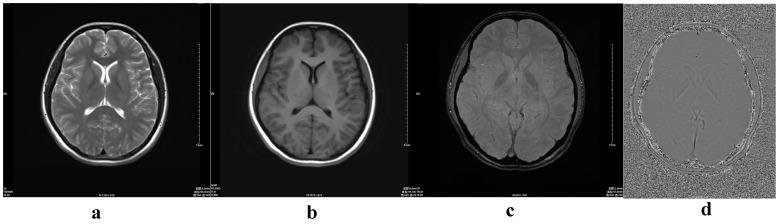

To quantify age-dependent iron deposition changes in healthy subjects using Susceptibility Weighted Imaging (SWI).

In total, 143 healthy volunteers were enrolled. All underwent conventional MR and SWI sequences. Subjects were divided into eight groups according to age. Using phase images to quantify iron deposition in the head of the caudate nucleus and the lenticular nucleus, the angle radian value was calculated and compared between groups. ANOVA/Pearson correlation coefficient linear regression analysis and polynomial fitting were performed to analyze the relationship between iron deposition in the head of the caudate nucleus and lenticular nucleus with age.

Iron deposition in the lenticular nucleus increased in individuals aged up to 40 years, but did not change in those aged over 40 years once a peak had been reached. In the head of the caudate nucleus, iron deposition peaked at 60 years (p<0.05). The correlation coefficients for iron deposition in the L-head of the caudate nucleus, R-head of the caudate nucleus, L-lenticular nucleus and R-lenticular nucleus with age were 0.67691, 0.48585, 0.5228 and 0.5228 (p<0.001, respectively). Linear regression analyses showed a significant correlation between iron deposition levels in with age groups.

Iron deposition in the lenticular nucleus was found to increase with age, reaching a plateau at 40 years. Iron deposition in the head of the caudate nucleus also increased with age, reaching a plateau at 60 years.